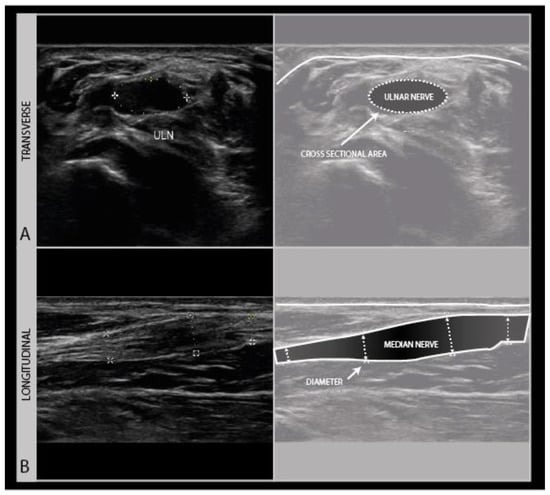

In recent wounds, stitches, surgical staples and drains may be still in place, that are usually echodense and scatter soundwaves from the surface, thereby limiting visual access to the underlying nerve (Figure 11).

Figure 11.

Severe knee torsion injury with a large tissue defect (A): post-surgical debridement ultrasound image of the posterior knee, with a tissue drain artefact obscuring the view of the underlying peroneal nerve (B) and a loss of anatomical features (C).

Ultrasound of fresh wound areas may be complicated by hematoma, giving a diffuse grayish shadowing of the image (Figure 12), and a loss of recognizable anatomical features (Figure 11 B).